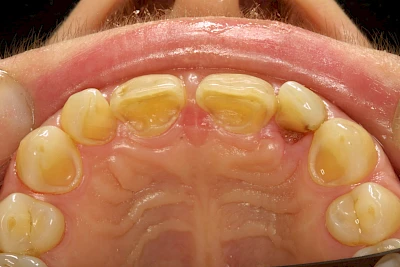

Auswaschung (Erosion) dagegen ist eine Verschleißerscheinung der Zähne aufgrund von immer wiederkehrenden Säureangriffen durch die Nahrung, verstärkt zum Beispiel durch den Genuss säurehaltiger Getränke oder Speisen. Auch bei Menschen mit einer Essstörung (z. B. Bulimie) können die Zähne durch die Magensäure ausgewaschen erscheinen.

Eine Sonderform sind sogenannte keilförmige Defekte im Bereich der Zahnhälse. Hier geht man davon aus, dass Knirschen und Pressen in Kombination mit falschen Putzgewohnheiten (zu hoher Putzdruck, Verwendung von Zahnpasta mit hohen Abrasionswerten) eine Rolle spielen.